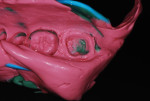

Treatment recommendations included placement of a composite restoration on the mesial of tooth No. 2, endodontic treatment on tooth No. 3 (Figure 1) followed by placement of a post/core, and restoration with a full-coverage crown and re-preparation of tooth No. 31 for a new crown (Figure 2).

Crown preparation was performed on tooth No. 3, placing the margins at approximately 0.5 mm apical to the gingival margin (Figure 3). Access to the mesial of tooth No. 2 allowed for caries removal while preserving the mesial marginal ridge of the tooth. G-ænial™ Bond (GC America) was applied to the cavity prep and allowed to sit for 10 seconds. It was air-thinned for 5 seconds and then light-cured for 10 seconds. As the area to be restored was in a very low wear area, it was decided to use a flowable resin. G-ænial™ Universal flo Flowable composite (GC America) was dispensed into the preparation, and a brush tip was used to smooth the uncured composite, which was then light cured for 20 seconds. Tooth No. 31 was re-prepared, lowering the margins approximately 1 mm subgingivally and paralleling the axial/proximal walls to increase retention for the new crown (Figure 4).